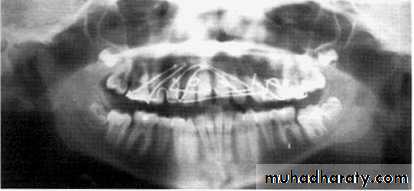

In a good panoramic radiograph:

The mandible is “U” shaped.The condyles are positioned about equal distance from the inside edges of the image and 1⁄3 of the way down from the top edge of the image.

The occlusal plane exhibits a slight curve or “smile line,” upwards.

The roots of the maxillary and mandibular anterior teeth are readily visible with minimal distortion.

Magnification is equal on both sides of the midline.